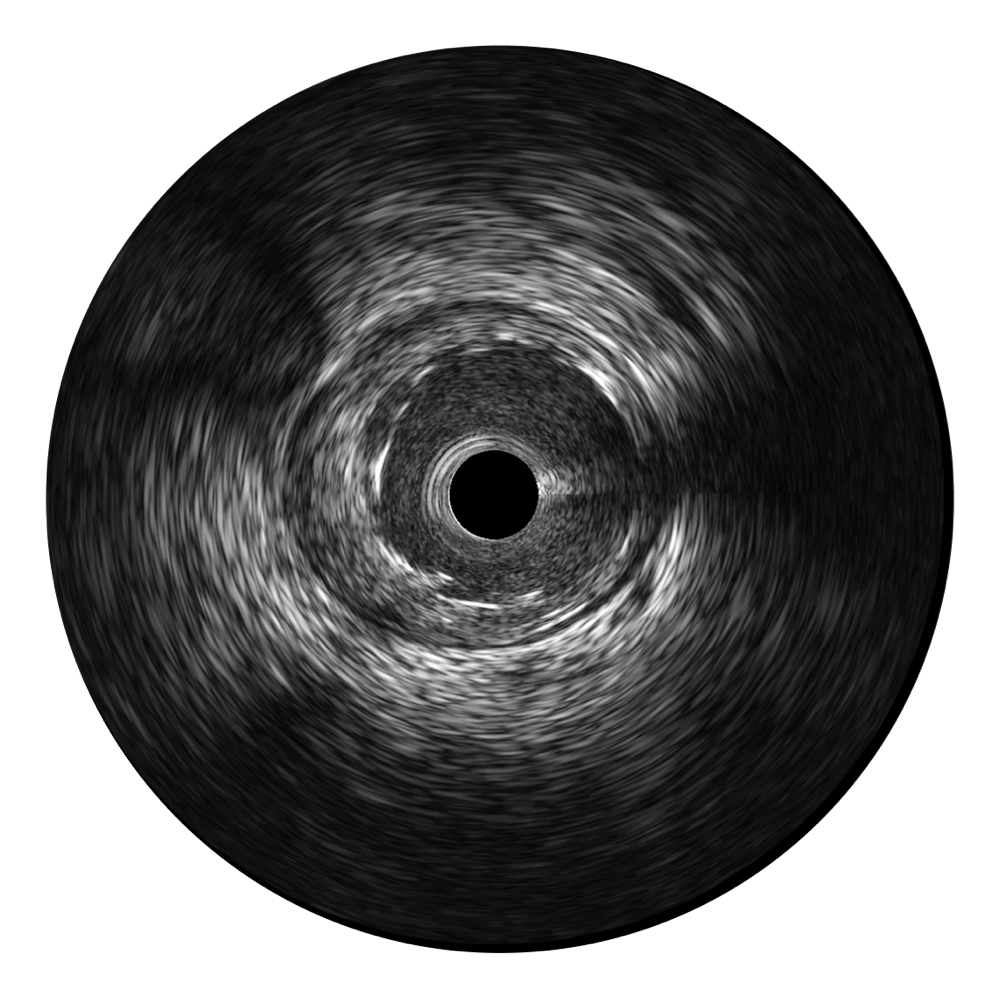

1xBET超宽频成像技术覆盖20-80MHz1或20-90MHz2频率范围, 提供优异的分辨力同时也保证充足的穿透深度

对比传统IVUS导管成像,1xBET宽频IVUS图像的近场支架梁显影更细腻,远场中膜外血管仍清晰可辨,兼顾远中近,兼顾分辨力与穿透深度